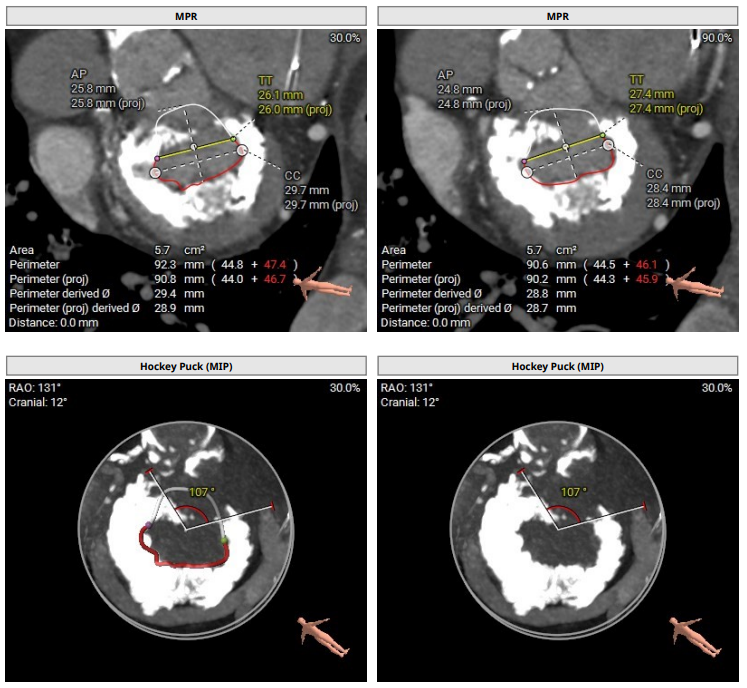

a snapshot from our recent #BASILICA case of a native aortic valve @UHZ_UNIFreiburg @dirkwestermann @HilgendorfIngo @PCRonline #TAVI #echofirst

Severe mitral regurgitation with severe mitral annular calcifications (MAC) adequate for anchoring with S3 valve. CT showing prohibitive risk of LVOT obstruction despite septal ablation (predicted neo-LVOT <100) therefore the patients would have required leaflet laceration.